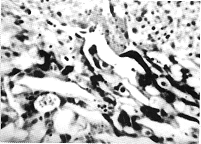

附图 平滑肌组织间有细胞滋养细胞(郎罕细胞)与合体滋养细胞。HE ×300